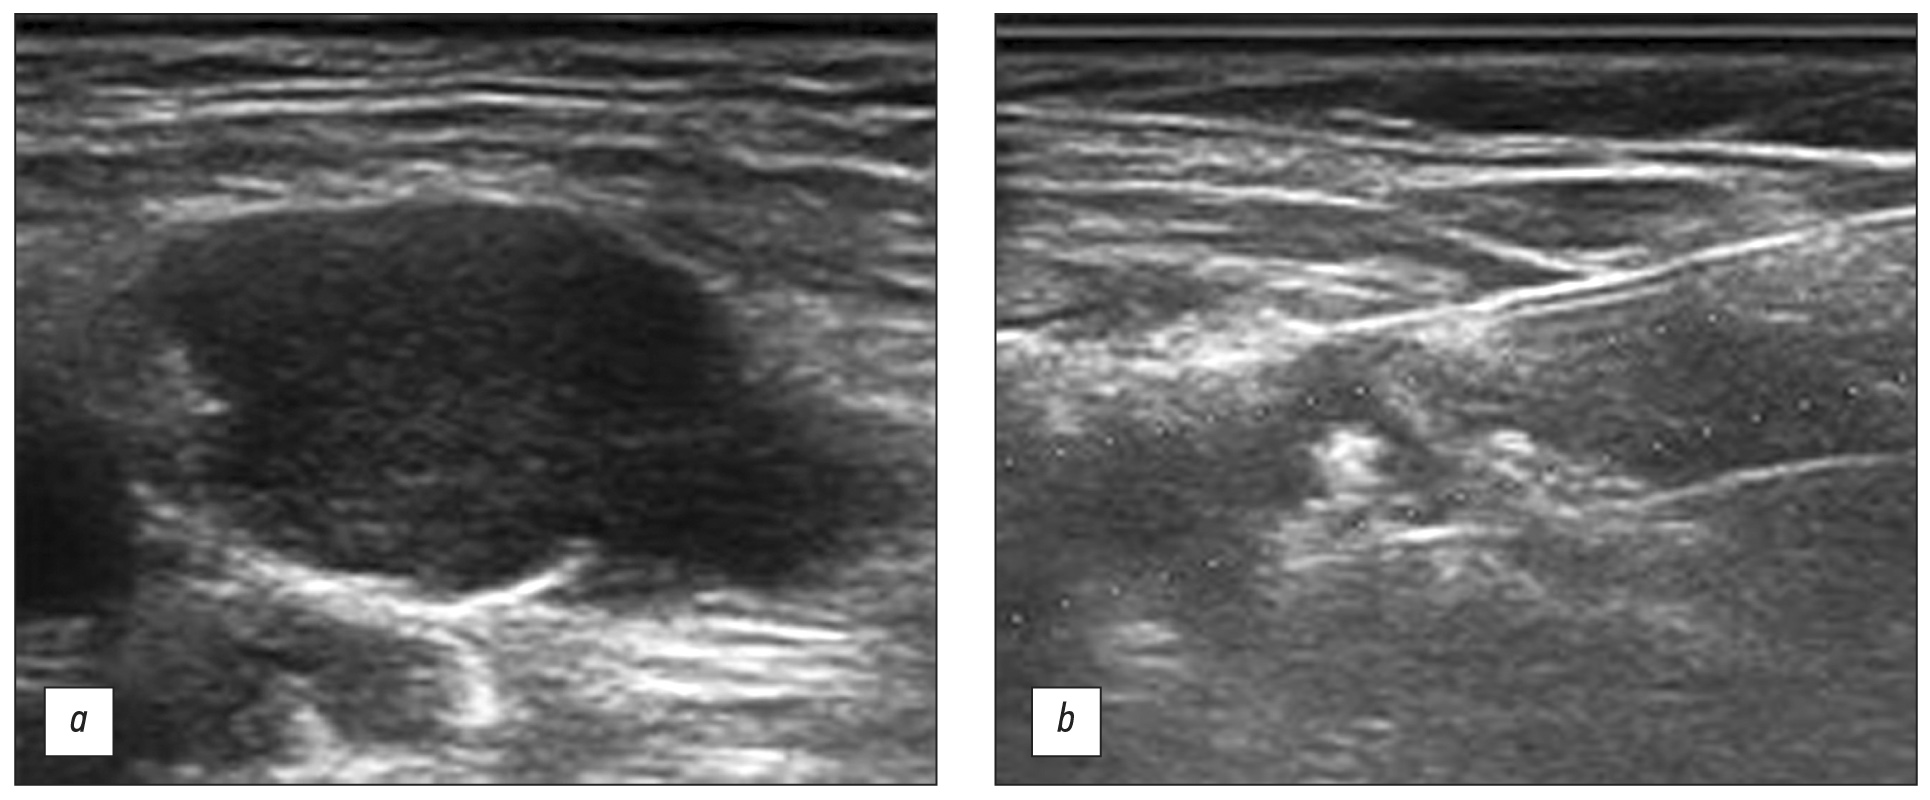

HPT术前成像的标准、最经济和最安全的方法是超声(图 2)。

图 2甲状旁腺功能亢进的甲状旁腺功能亢进的超声成像:a - 原发性甲状旁腺功能亢进; b - 继发性甲状旁腺功能亢进。